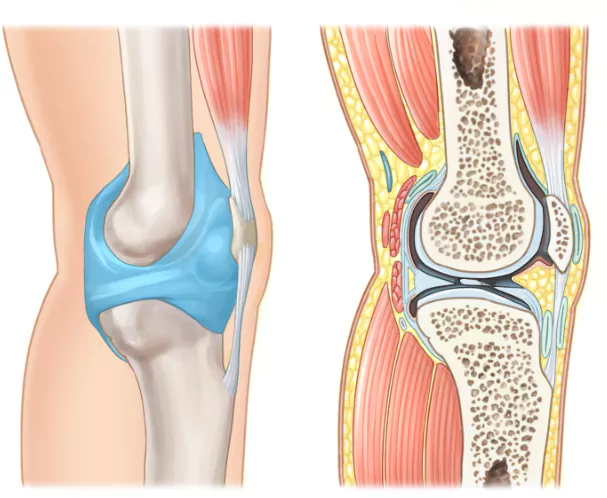

무릎 관절염은 많은 사람들에게 영향을 미치는 흔한 관절 문제 중 하나입니다. 이러한 질환이 있는 환자들은 적절한 운동을 통해 무릎 관절을 더욱 강화하고 통증을 완화하는데 도움을 줄 수 있습니다. 이 글에서는 무릎 관절염에 좋은 운동 10가지 및 주의사항에 대해서 자세히 살펴보겠습니다.

정기적인 무릎 관절염 운동은 기본적인 치료 방법이지만 오해에 기반한 운동 방법은 실제로 무릎 관절염을 악화시킬 수 있습니다.

무릎 관절염 환자가 피해야 할 운동에는 과도한 스쿼트 와 런지, 험난하고 부담이 되는 산행 또는 가파른 산 비탈길에서의 걷기, 장거리 조깅, 관절에 충격을 일으킬 수 있는 배구, 농구, 축구, 풋볼, 테니스와 같은 운동등이 포함됩니다.